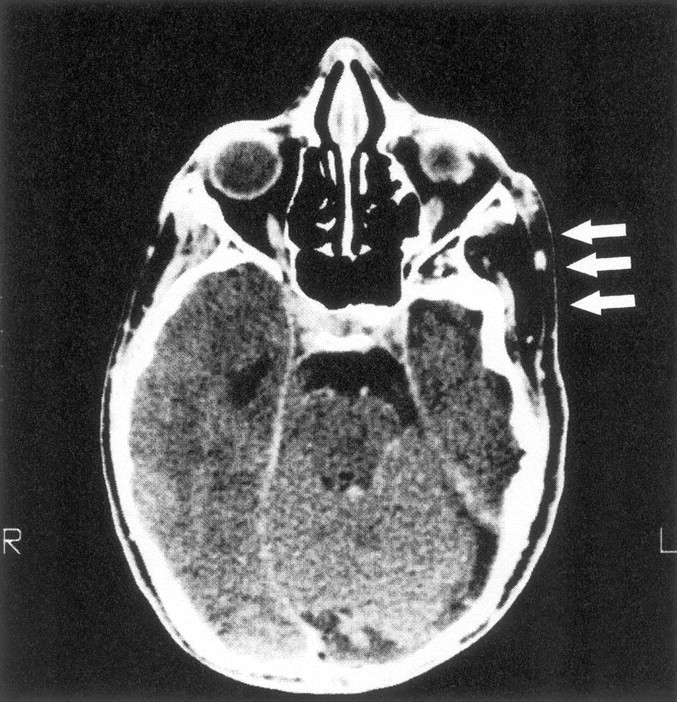

Thirteen of these 18 patients also had enlargement of the middle cranial fossa in primarily the anteroposterior dimension, with an appearance of the greater sphenoid wing typical of classic sphenoid dysplasia (Fig 2). Enlargement of the middle cranial fossa was always associated with tumor in the ipsilateral superficial temporal fossa, and some of these patients also had radiologically abnormal squamosa and temporal squamosal sutures (Fig 3). One patient had discrete expansion of the middle cranial fossa with no tumor detected near the sphenoid bone (Fig 4), but 12 of the 13 patients had tumor contiguous to altered sphenoid bone. The temporal lobe did not herniate forward behind the distorted greater sphenoid wing in patients with expanded middle cranial fossae because every patient had an arachnoid cyst between the anterior temporal lobe and the anterior wall of the middle cranial fossa. Tumor was present in the pterygoid fossa of nine of the 13 patients with sphenoid dysplasia.

Enlargement of the left middle cranial fossa with temporal arachnoid cyst, absence of the left sphenoid wing, and flattening of the temporal bone. There is tumor invasion of the orbit with reduced orbital volume, and the left eye was enucleated. The insert shows an abnormal temporal squamosa suture (arrowheads) underlying tumor in the left superficial temporal fossa.